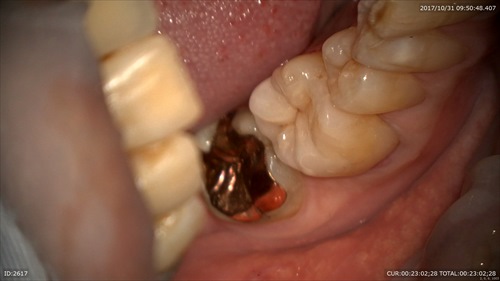

本日セットしました。段差などないかをマイクロスコープで確認します。

痛みがないと喜んで頂けました。ありがとうございます。

マイクロスコープだと目の前でこの様に術前(右)術後(左)をお見せできるので分かりやすいですね。